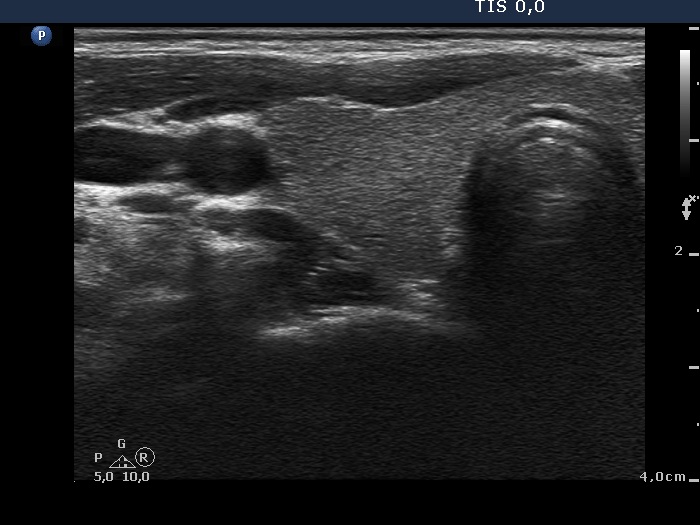

Ultrasonography: The thyroid was echonormal. There was a moderately hypoechogenic inhomogeneous nodule in the lower pole of the right lobe. There were two lymph nodes next to each other above the right thyroid in the submandibular area. The lymph nodes presented a regular hilum.

Follow-up investigation one year later. The size of the thyroid nodule remained unchanged while the lymph nodes have disappeared.

1. This is the typical presentation of a bacterially infected lymph node. In most of these cases we find multiple lymph nodes next or very close to each other. The presence of ill-defined hypoechogenic areas within the lymph nodes is an even more important sign of a bacterial lymphadenitis.

2. It is edifying to analyze the hyperechogenic figures in the thyroid lesion. While examining the patient, I interpreted these as microcalcifications. However, by preparing the case study I had to regroup these figures. These are in fact presentations of connective tissue and colloid crystals. (See the footnotes of the relevant images.)